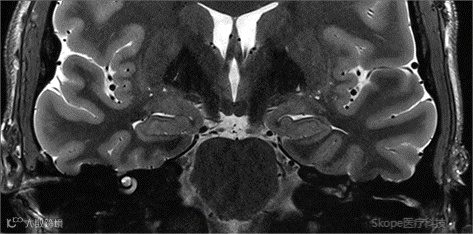

Sagittal T2 TSE

pTx有效改善了小脑区域图像均匀性。